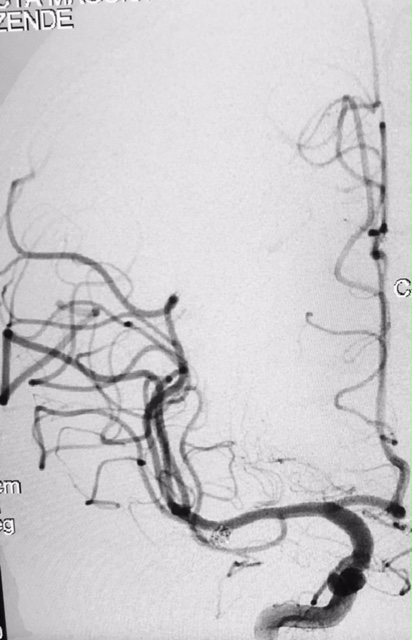

Tratamento de aneurisma cerebral com auxílio de balão duplo lumém e neurostent LEO